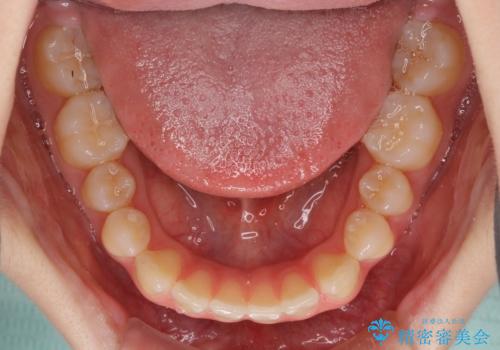

- 上の前歯の隙間を気にして来院された患者様です。

インビザラインにより、隙間を閉じながら、隙間の原因であるディープバイトを改善していくこととしました。

下顎の歯列が強く上顎に咬みこむことで隙間ができてしまうため、マウスピースの保定装置では後戻りのリスクが高くなってしまいます。

そのため、上下ともに前歯の裏側を細いワイヤーで固定し、その上から保定装置のマウスピースを使用していただくこととしました。